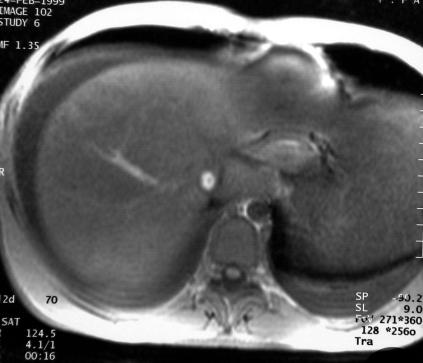

L'IRM est demandée pour faire le bilan.

T1 avant gado